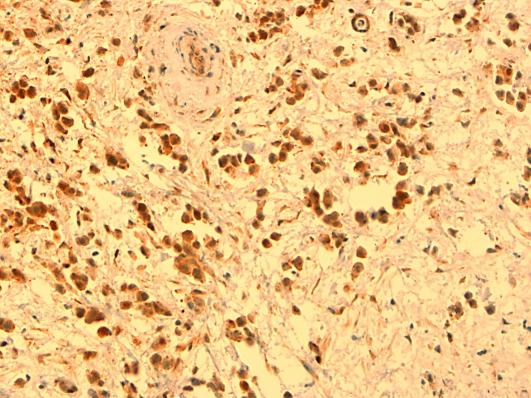

Primary mesothelioma of the pericardium is a rare tumor and carries a dismal prognosis. This case report presents a 38-year-old man who suffered from recurrent pericardial fluid. Initial symptoms were unspecific, with dry cough and progressing fatigue. Pericardiocentesis was performed, but analyses for malignant cells and tuberculosis were negative. After recurrence a pericardiectomy was planned. At operation, partial resection of tumor tissue surrounding the heart was performed. Histopathologic examination including immunohistochemical staining for calretinin showed a biphasic mesothelioma. During the postoperative period the patient's condition ameliorated, but symptoms recurred and the patient died 3 months after diagnosis and 15 months after the first symptoms. At autopsy, the pericardium was transformed by the tumor that also expanded into the mediastinum and had set metastases to the liver. A review of 29 cases presented in the recent literature indicates a higher incidence of malignant pericardial mesothelioma among men than women. Median age was 46 (range, 19-76) years. In pleural mesotheliomas, exposure to asbestos is a known risk factor. However, in primary pericardial mesotheliomas the evidence for asbestos as an etiologic factor seems to be less convincing (3 exposed among 14 cases). Symptoms are often unspecific and cytologic examination of pericardial fluid is seldom conclusive (malignant cells demonstrated in 4/17 cases). Partial resection of the tumor can give a period of symptom reduction. Only a few patients have been treated with chemotherapy. Median survival of patients with pericardial mesotheliomas is approximately 6 months.

原发性心包间皮瘤是一种罕见肿瘤,预后很差。本病例报告介绍了一名38岁男性,他患有复发性心包积液。初始症状不具特异性,有干咳和进行性疲劳。进行了心包穿刺术,但恶性细胞和结核分析均为阴性。复发后计划进行心包切除术。手术时,对心脏周围的肿瘤组织进行了部分切除。组织病理学检查包括钙视网膜蛋白免疫组化染色显示为双相性间皮瘤。术后患者病情有所改善,但症状复发,患者在诊断后3个月及出现首发症状后15个月死亡。尸检时,心包被肿瘤侵犯,肿瘤还扩展至纵隔并已转移至肝脏。对近期文献报道的29例病例的回顾表明,恶性心包间皮瘤男性发病率高于女性。中位年龄为46岁(范围19 - 76岁)。在胸膜间皮瘤中,接触石棉是已知的危险因素。然而,在原发性心包间皮瘤中,石棉作为病因的证据似乎不那么令人信服(14例中有3例接触过石棉)。症状往往不具特异性,心包积液的细胞学检查很少能确诊(17例中有4例发现恶性细胞)。肿瘤部分切除可使症状缓解一段时间。只有少数患者接受了化疗。心包间皮瘤患者的中位生存期约为6个月。